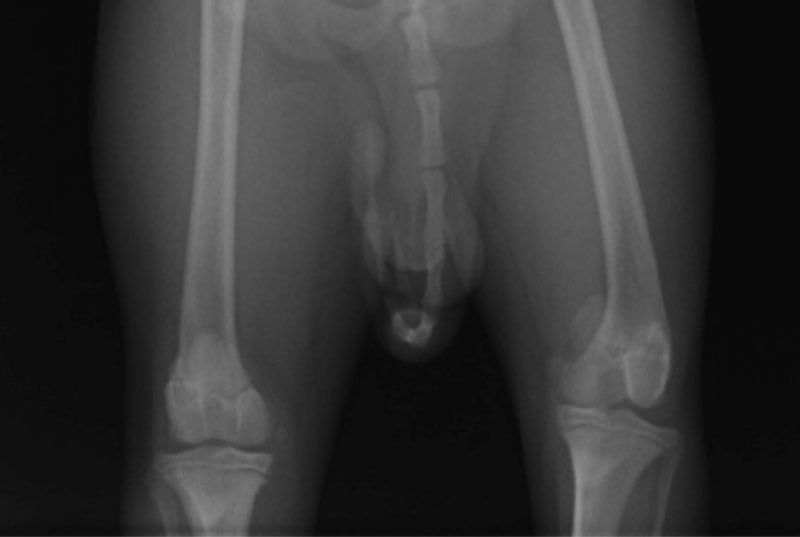

■ 症例22 ポメラニアン 1歳5か月 去勢雄

左後肢の挙上を主訴に来院した。整形学的検査、レントゲン検査より左右の膝蓋骨脱臼(左GradeⅡ〜Ⅲ、右Grade Ⅱ)を認めた。また、脛骨の前方引き出し試験の際に、引き出し兆候は認められないものの、疼痛が認められたため、前十字靭帯の損傷が疑われた。術中における、目視および関節内の操作によって、前十字靭帯の損傷や過伸展といった異常が認められなかったため、膝蓋骨脱臼の整復のみ実施した。手術手技は縫工筋及び内側広筋の解放、脛骨粗面の外側転位、滑車ブロック形造溝術、内外側関節包の縫縮を実施した。本症例は跛行もなく経過良好である。しかし、頸骨高平部の角度(TPA)が 右26.2°、左24.9°であり、解剖学的に前十字靭帯損傷のリスクが高いことから今後の経過に注意が必要である。